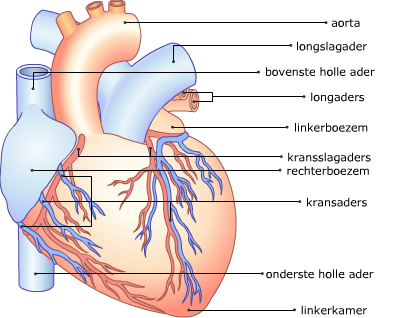

Buitenaanzicht van het hart

Je ziet hier een schematische afbeelding van het hart en de bloedvaten er omheen. Leer de namen van de verschillende onderdelen.

Buitenaanzicht van het hart